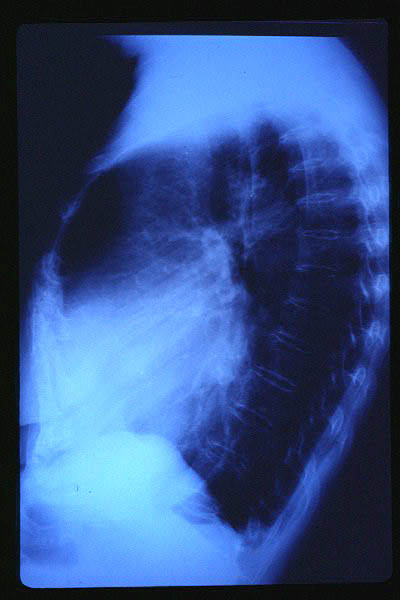

Osteoporosis. Cifosis.